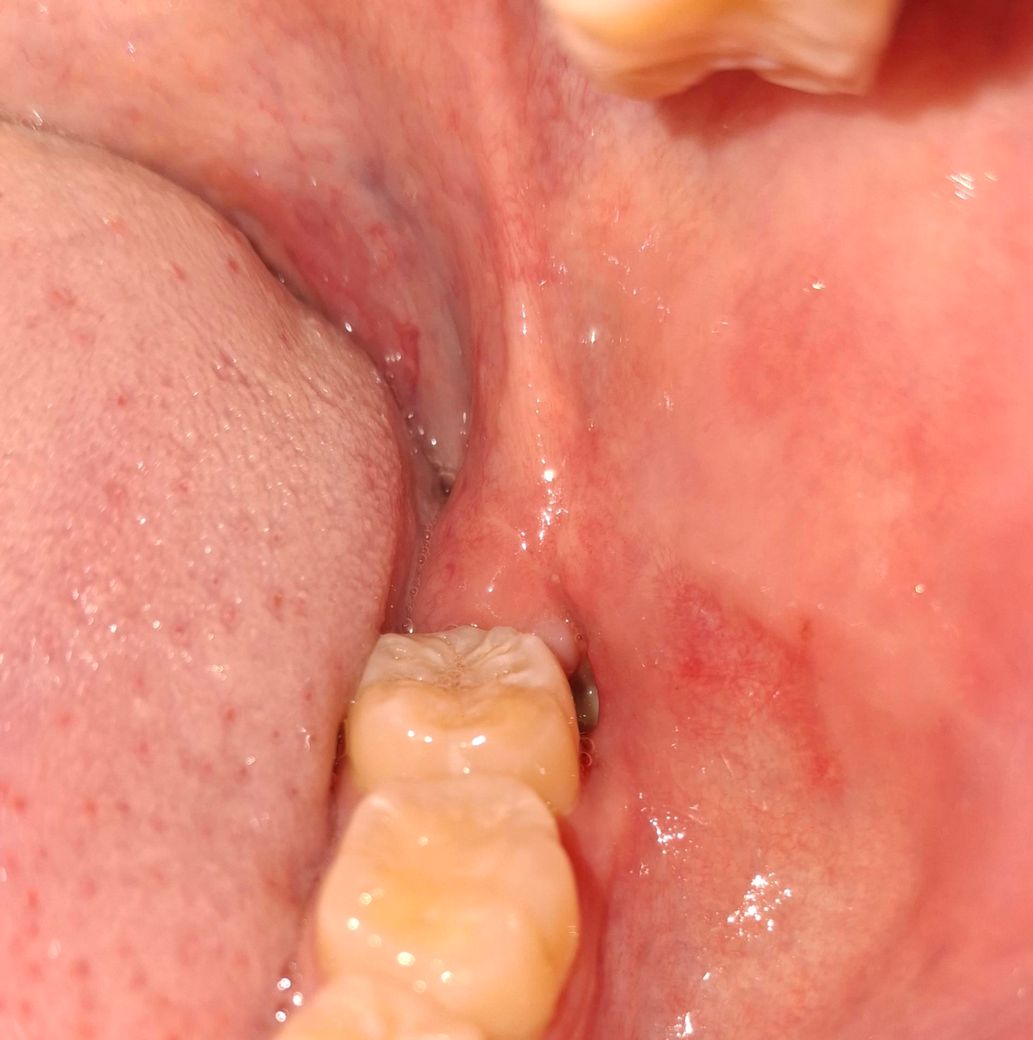

사랑니 발치 이후 생긴 구멍의 하얀색 조직에 대하여

사랑니 발치 이후 20일 가량 경과 하였고, 그 과정에서 발생한 구멍의 끝에 하얀색 조직이 생겼습니다.

통증은 없습니다만, 궁금하여 이렇게 올려봅니다.

• 1번 째 사진

아직 사랑니 발치를 한곳이 다 아물지 않은 상태 같습니다. 아물면서 생기는 현상이니 걱정하지 않으셔도 될것같습니다.

아직 잇몸이 완전히 아물지 않아서 그렇게 보이는 것으로 시간이 지나면 다 회복될 것입니다.

사랑제를 발치하면 발치한 부위가 아무나 과정에서 하얀색 가피가 형성될 수 있습니다. 크게 문제가 되는 것은 아니니 걱정하지 않으셔도 될 것으로 생각됩니다. 발치를 했다면 발치한 부위가 자극이 되지 않도록 하는 거에 좋습니다.